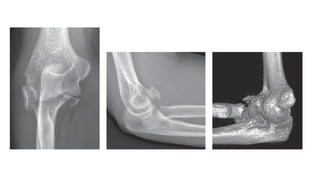

RADIOGRAPHIC EVALUATION

• Anteroposterior and lateral radiographs.

• GREENSPAN VIEW / RADIOCAPITELLAR VIEW-

forearm in neural rota)on and the radiographic

beam angled 45 degrees chephalad.

• It provides visualisa)on of the radio capitellar

ar)cula)on.